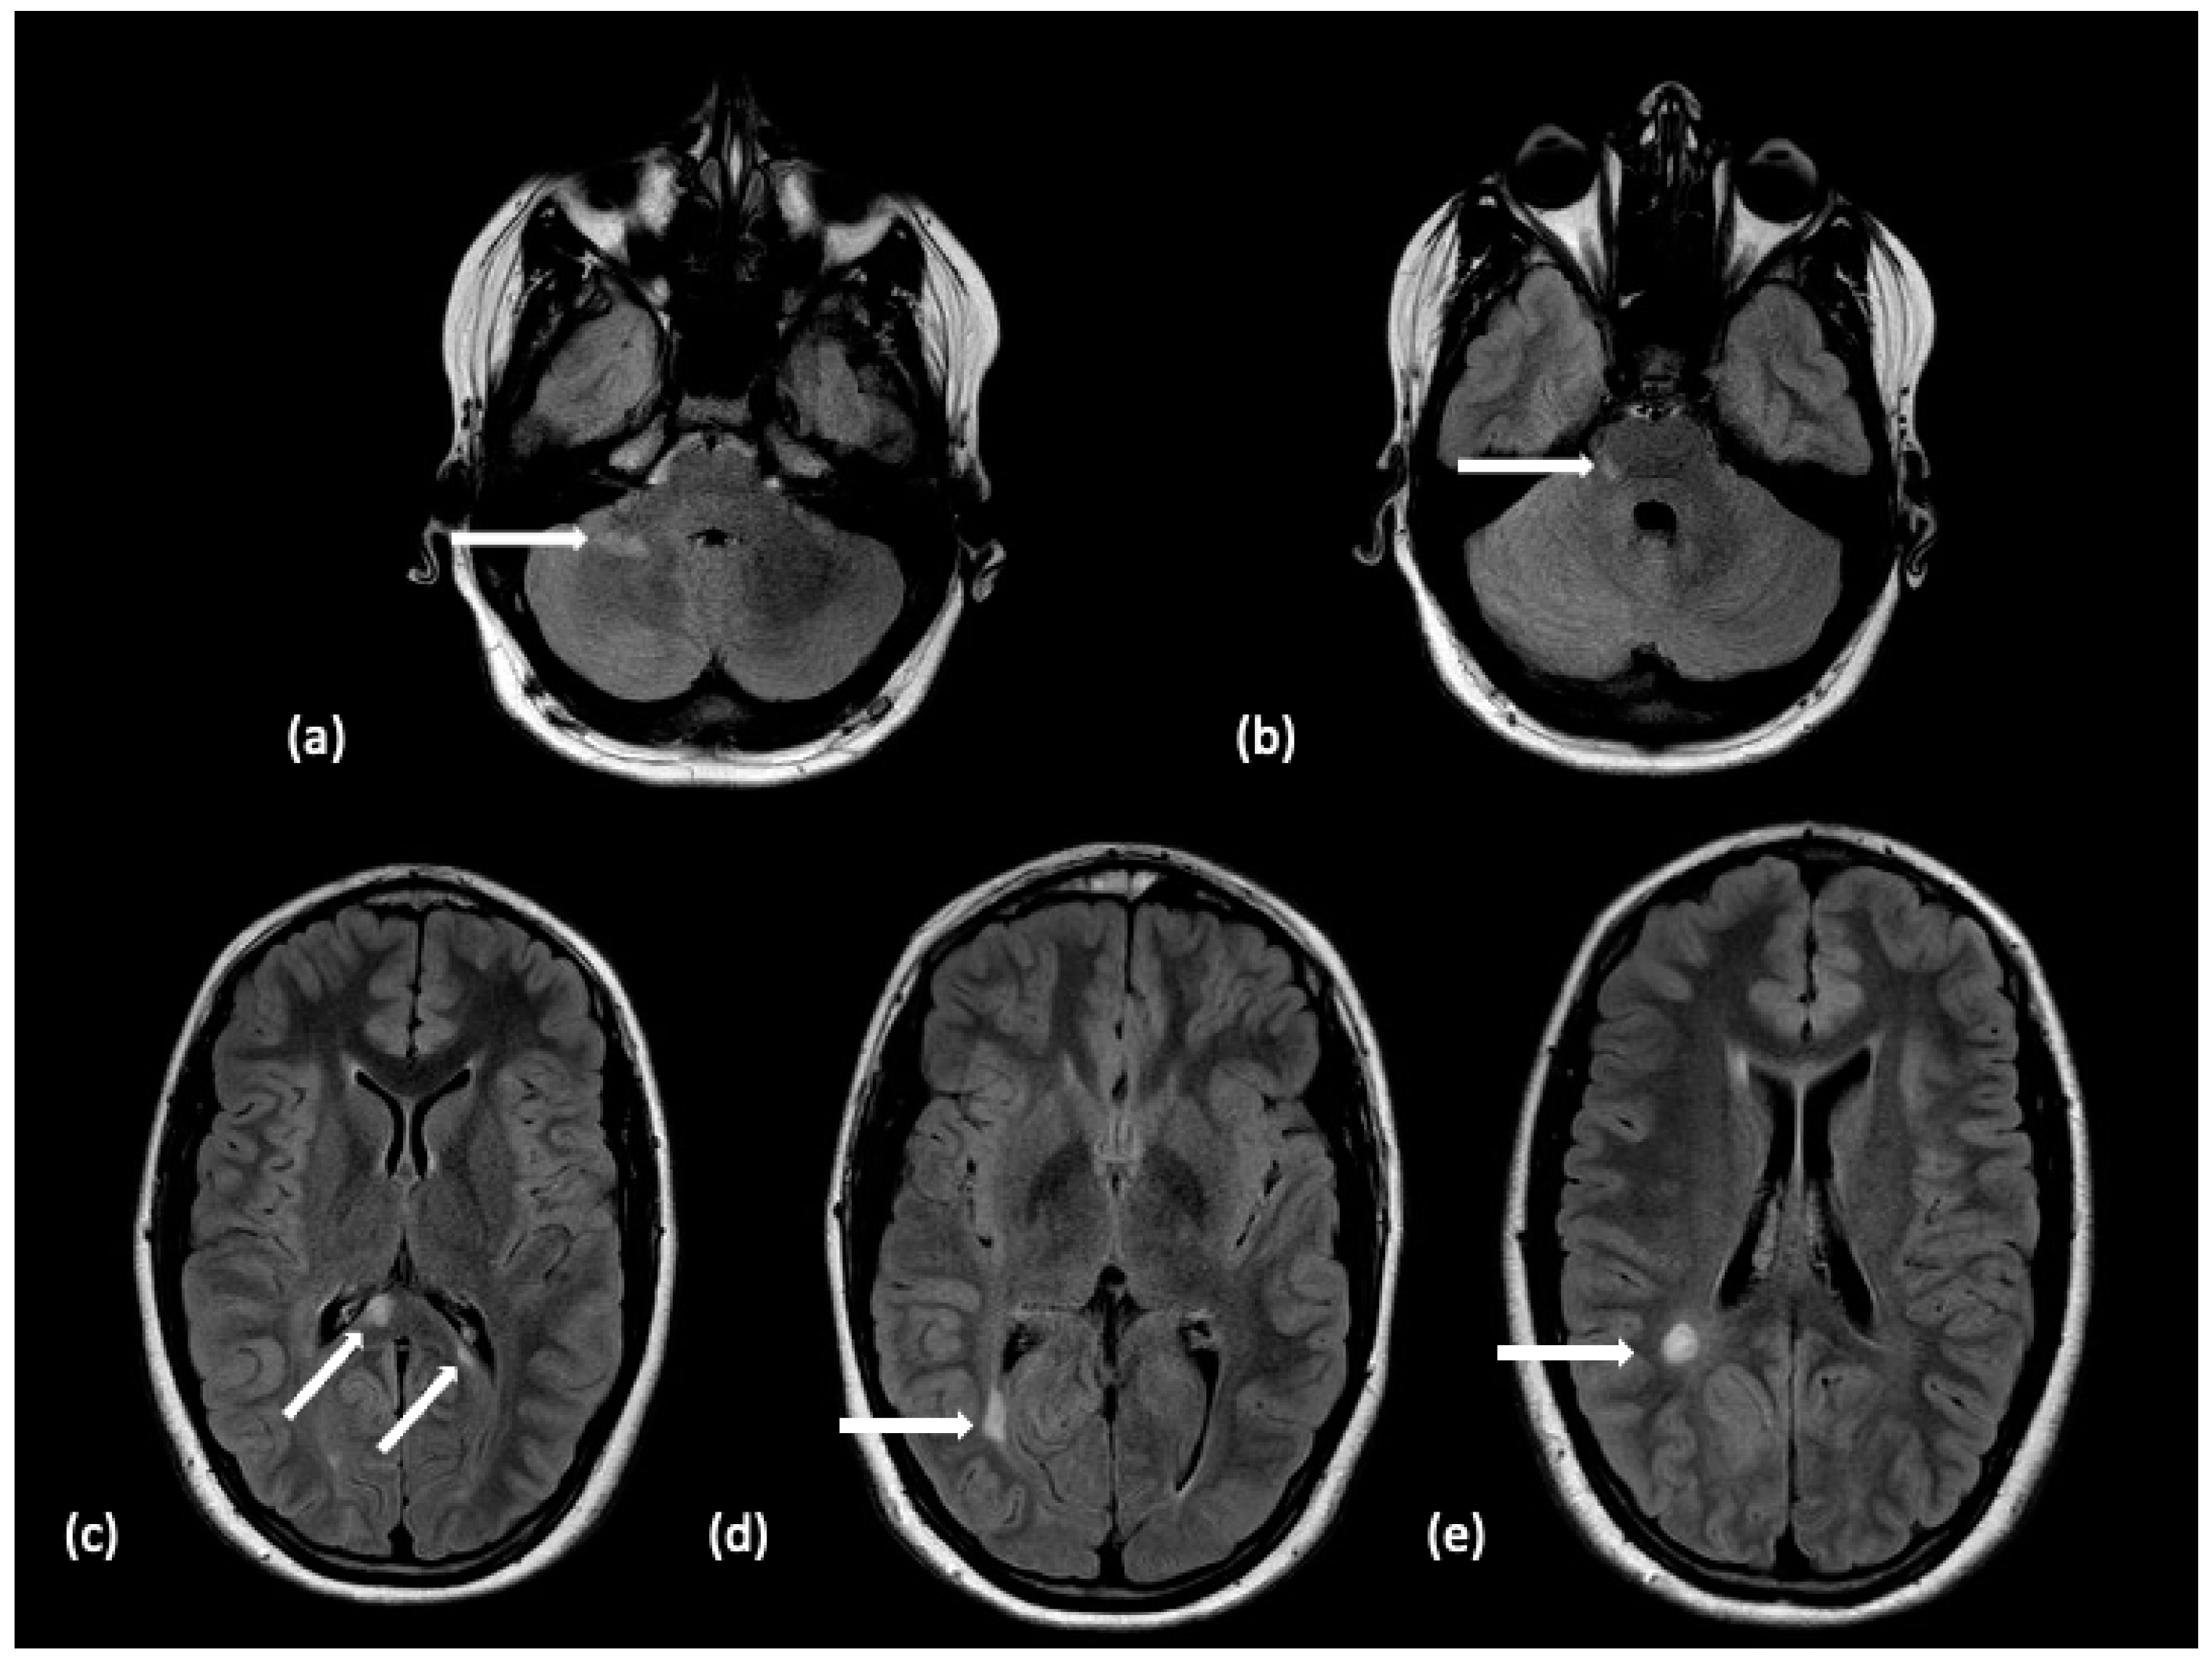

| Pediatric-onset Multiple Sclerosis | Two distinct events; Relapsing | Periventricular lesions in deep white matter, Juxtacortical (subcortical white matter) lesions, infratentorial lesions that are focal, ovoid-shaped lesions. Spinal cord lesions spanning less than 3 vertebral segments. | Active lesions show enhancement | Small, ovoid lesions perpendicular to long axis of corpus callosum (Dawson’s fingers); Lesions in subcortical U-fibers; Silent lesions; Black holes (T1 hypointense lesions); Variable age of lesions |